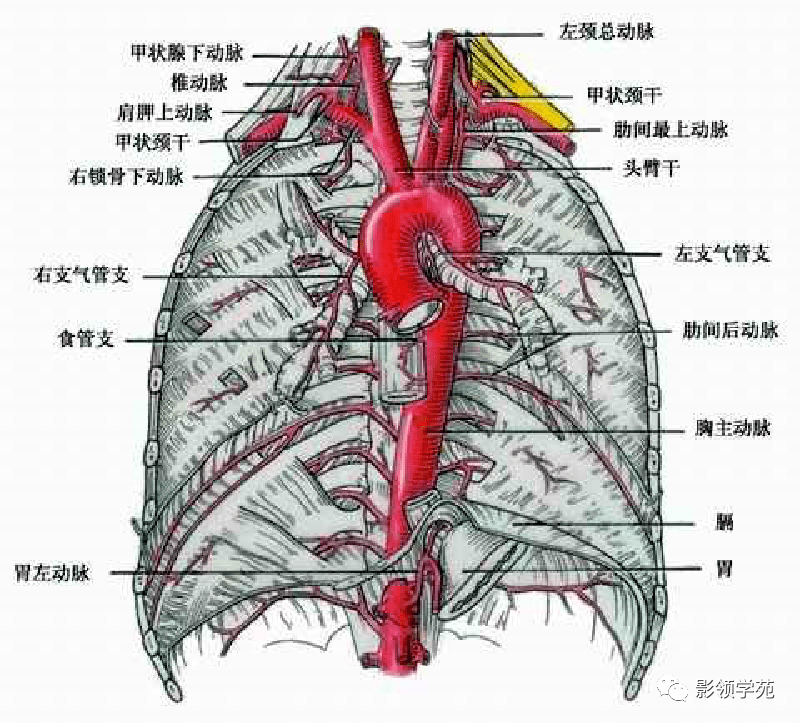

心血管系统

心血管系统